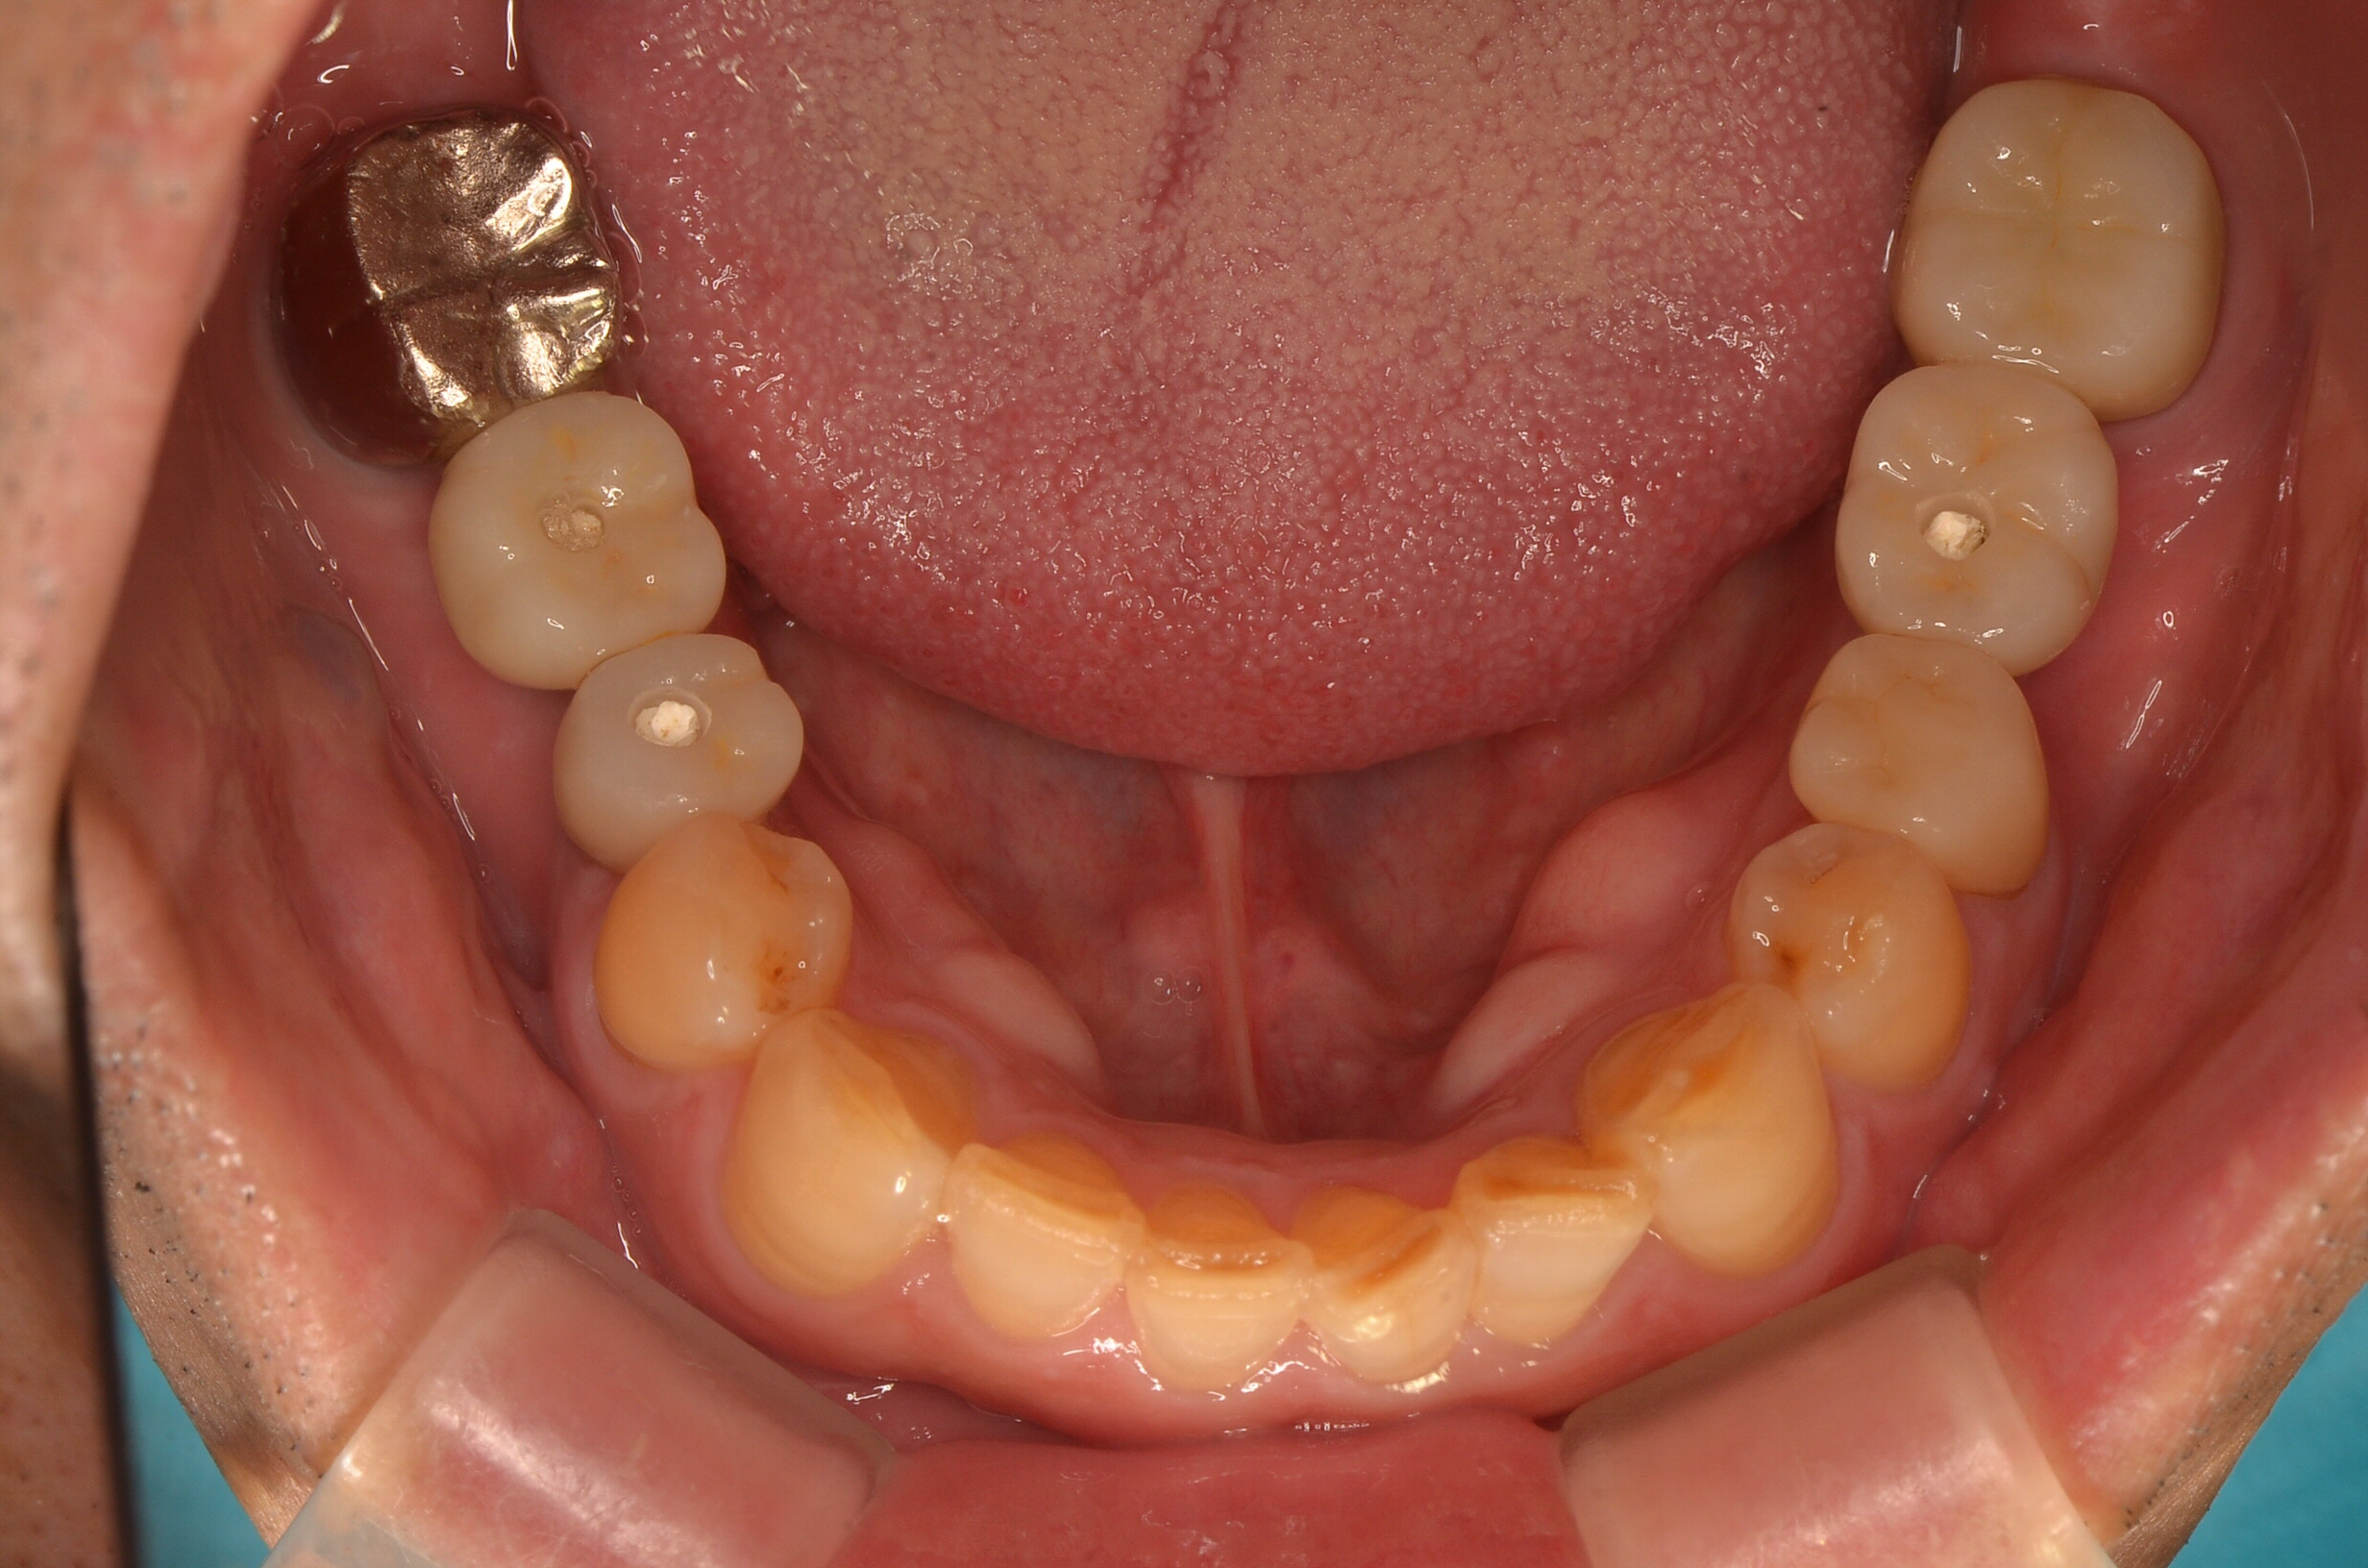

インプラント

Before

After

年齢

65歳

主訴

奥歯で硬いものが噛めない

治療期間

約6ヶ月

治療費

約1,500,000円

概要

奥歯で固い食べ物が噛めず、年齢とともに噛み合わせや咀嚼機能の低下を実感されていました。

インプラント治療を行うことで、噛む力の回復・機能改善が期待できると判断しました。

患者様と相談のうえ、骨の状態や全身の健康状態に配慮しながら治療計画を立て、骨造成を行い、インプラント体を安全に埋入。その後、人工歯(上部構造)を装着しました。

治療後は、硬い食事もしっかり噛めるようになり、「食事の楽しみが戻った」と喜んでいただけました。